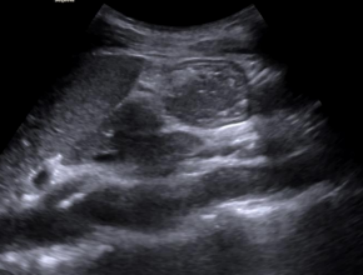

2. 胃窦内呈均匀一致的无回声或低回声4,或低回声中出现多个移动的点状高回声形似“繁星”5,宜评判为无渣清亮液体。当胃窦内回声呈均质增强时(6), 宜评判为浓稠液体

图片

6  浓稠液体,回声均质增强